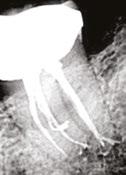

Figure 2: The newly redesigned Booster Tip with 6 cutting edges and 6 facets Figure 3: The new XP-3D Shaper+ sequence. Both files can be used at 1000 rpm and 1Ncm torque. Once a glide path of 15.04 is reached, the shaper is taken to working length using 2-5 strokes, followed by 8 additional long strokes to get 30.04

Another cutting-edge technology included in the XP-3D Shaper+ is the tip which has a unique geometry. It comes with the Booster Tip made of six cutting edges aligned with six facets — versus three for the conventional XP-3D Shaper. This tip enables the instruments to start cleaning and cutting dentin at 0.6 mm from the tip with an initial cutting diameter of 0.12 mm, ensuring 0.30 mm diameter is reached at 0.6 mm from the tip (Figure 2). A glide path of at least 15.04 is required, which will be gradually increased to achieve 30.04. This design makes treatment shorter and easier to perform, reducing the risk of errors and incidents while preserving the natural shape of the canal. The XP-3D Shaper+ is employed at a speed of 1000 rpm and 1Ncm torque and can be used up to eight canals according to the following protocol: once working length is confirmed, a glide path up to size 15.04 is recommended. This is easily achievable with the XP-3D Scout (Brasseler USA, Savannah, Georgia) 15.04 file. Following that, the XP-3D Shaper+ can be used giving 2-5 strokes until working length is reached. The canal is then flushed with NaOCl or another irrigation solution like Triton® (Brasseler USA, Savannah, Georgia) and the XP-3D Shaper+ reintroduced with eight full strokes to working length, at which point the canal would have been anatomically cleaned and instrumented to a size 30.04.7 The advantage of using the aforementioned 15.04 file is that it functions at the same speed and torque as the XP-3D

Shaper+, hence streamlining the procedure (Figure 3). This new instrument offers clinicians the possibility of letting the canal shape the file and solves two of the previously mentioned challenges: the deficiency of traditional NiTi instruments and their weakening of the dental structure.